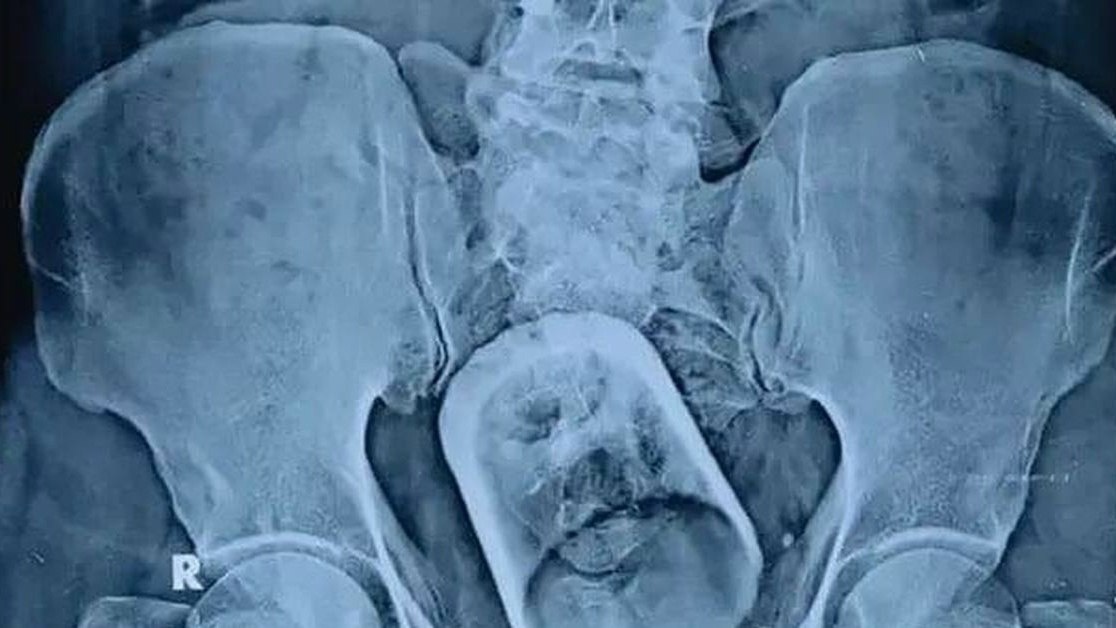

😰В Башкирии мужчина два дня ходил со стаканом в заднем проходе в надежде, что он выйдет сам. Но бедолагу пришлось экстренно госпитализировать — стекло лопнуло внутри

В Уфе 35-летний мужчина признался врачам в местной больничке, что развлекался наедине с гранёным стаканом. Экстрим-романтик закончился плачевно: сосуд застрял. Мужичок надеялся, что последствия самоликвидируются, но чуда не случилось. Стеклянный оптимизм дал трещину, когда экспериментатор пытался извлечь инородное тело. Стакан лопнул в прямой кишке.

Бедолагу экстренно прооперировали, стакан и остатки стекла извлекли. Сейчас мужик чувствует себя лучше. Его выписали, но оставили под амбулаторным наблюдением. Пациенту-экспериментатору предстоит долгий курс реабилитации.